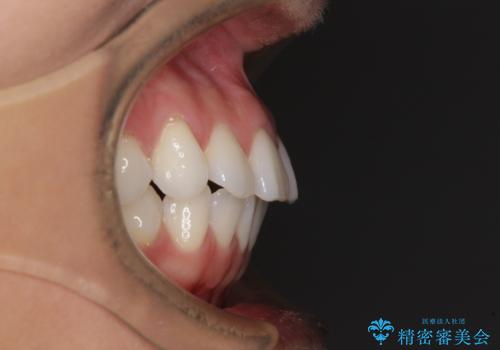

【モニター】インビザラインで口を閉じやすく

- 前に出ている上顎前歯が気になるとのことで来院された患者様です。

インビザラインを用い、IPR(歯と歯の間を削る)と歯列全体を後方に移動させることで、可能な限り前歯の突出感を改善することとしました。

元々の歯列も整っており、横顔の印象の出っ歯ではなかったため、仕上がりに満足できない可能性があると心配しておりましたが、口が閉じやすくなり、患者様には大変満足していただきました。